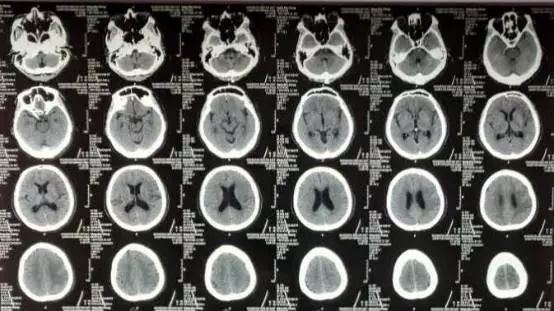

男性患者,51岁,以“言语不能、右侧肢体偏瘫3.5小时”入院,神经系统查体:神志清楚,完全性失语,查体不能合作,右侧上下肢体肌力2-3级。NIHHS评分=12分。

急诊颅脑CT排除出血,患者已超出静脉溶栓时间窗,予性颅脑MRI+MRA示“左侧大脑中动脉供血区大面积脑梗死,左侧大脑中动脉闭塞”。